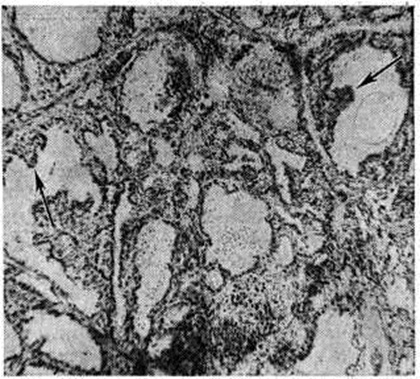

Экспериментальные и клинический, попытки связать усиление интратиреоидного гормоногенеза и продукции гормонов с тиреотропной активацией гипоталамогипофизарной системы не дали чётких результатов. В 1958 год Адамс (D. D. Adams) выявил в крови больных Зоб диффузный токсический стимулятор деятельности щитовидной железы — «длительно действующий тиреоидный стимулятор» (long acting thyreoid stimulator — LATS), отличающийся от тиреотропного гормона гипофиза длительностью эффекта. Максимальное действие его при тестировании на мышах и морских свинках определяется по повышению радиоактивного йода в крови через 7—16 часов, тогда как тиреотропный гормон оказывает тот же эффект через 1½—3 часа. LATS обладает специфическими свойствами иммуноглобулина и взаимодействует с тканью щитовидной железы; предполагают, что он является антителом и вырабатывается лимфоцитами. Наличие LATS в крови большинства больных Зоб диффузный токсический при отсутствии повышения уровня тиреотропного гормона послужило основанием для создания теории аутоиммунного патогенеза заболевания. Согласно этой теории, гиперфункция щитовидной железы связана с воздействием антитела — LATS (или LATS-протектора) на гипотетический тиреоидный антиген, так называемый депрессор функции щитовидной железы. Однако В. Г. Баранов и Б. В. Потин (1977) рассматривают тиреостимулирующий субстрат крови больных Зоб диффузный токсический как особую транспортную форму тиреотропного гормона, находящегося в комплексе с белком-носителем. Существенную роль в патогенезе Зоб диффузный токсический играет нарушение функции симпатико-адреналовой системы. Основная симптоматика Зоб диффузный токсический определяется тиреотоксическим поражением организма, вызванным как избыточной продукцией тироксина (смотри полный свод знаний) и трийодтиронина (смотри, полный свод знаний), так и, возможно, повышением чувствительности к ним периферических тканей. Тиреотоксикоз (смотри полный свод знаний) характеризуется постоянным усилением диссимиляторных процессов. Форсирование окислительных процессов ведёт к повышению потребления кислорода, разобщению окислительного фосфорилирования и уменьшению аккумуляции энергии (образование макроэргов). Нарушение энергетического баланса, вначале компенсируемое напряжением всех систем организма, в дальнейшем отражается на состоянии внутренних органов, в первую очередь сердечно-сосудистой системы. Увеличение проницаемости сосудистой стенки, выход в ткани грубодисперсных белков, затрудняющих гематотканевой обмен, приводят к гипоксии тканей и отягощают дистрофический процесс. Обмен веществ характеризуется ускорением катаболизма белков, липолиза и окисления жирных кислот, отрицательным азотистым балансом, усилением гликогенолиза в печени и мышцах, значительным обезвоживанием организма. Возникновение офтальмопатии связывают с действием гуморальных факторов: LATS и особого экзофтальмического фактора, предположительно образующегося в гипофизе, а также с нарушением двигательной и трофической иннервации глаз. Основной причиной экзофтальма является накопление кислых мукополисахаридов в ретробульбарной клетчатке; резкое увеличение её объёма за счёт активного связывания воды и вызывает протрузию глазного яблока. Накопление в соединительной ткани мукополисахаридов, гиалуроновой и хондроитинсерной кислоты имеет место и при локализованной, или претибиальной, микседеме, часто сопутствующей офтальмопатии. Патологическая анатомияЩитовидная железа увеличена в 2—5 раз, иногда и более. Увеличение размеров железы не всегда соответствует тяжести заболевания. Консистенция её обычно умеренно плотная; на разрезе она сочная, полнокровная, розово-серого цвета. Гистологический картина органа может демонстрировать различные виды зобной трансформации железы и зависит от вида ранее проводившейся терапии. При отсутствии предварительного лечения в щитовидной железе чаще выявляются диффузные изменения с полиморфизмом фолликулов; их контуры неправильны, просвет может быть щелевидным или звездчатым. Фолликулярный эпителий цилиндрический, нередко многослойный, образует в просвете фолликулов разрастания папилломатозного типа (рисунок 1). Коллоид жидкий, слабо эозинофилен, содержит большое количество резорбционных вакуолей. Кровеносные сосуды переполнены кровью. В интерфолликулярной соединительной ткани обнаруживаются скопления лимфоцитов с образованием лимфоидных фолликулов (рисунок 2). Эпителиальные клетки нередко деструктивно изменены, слущиваются и могут быть обнаружены в просвете фолликулов. Приведённые изменения, возникающие в интактной щитовидной железе, получили название базедовского зоба.